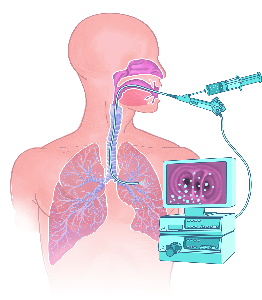

Detailreiche Fotografien aus der medizinischen Praxis ergänzen die Texte; moderne, genaue,

wissenschaftliche Zeichnungen geben Einblick in die Anatomie und die Funktion der Lunge und

anderer Organe.